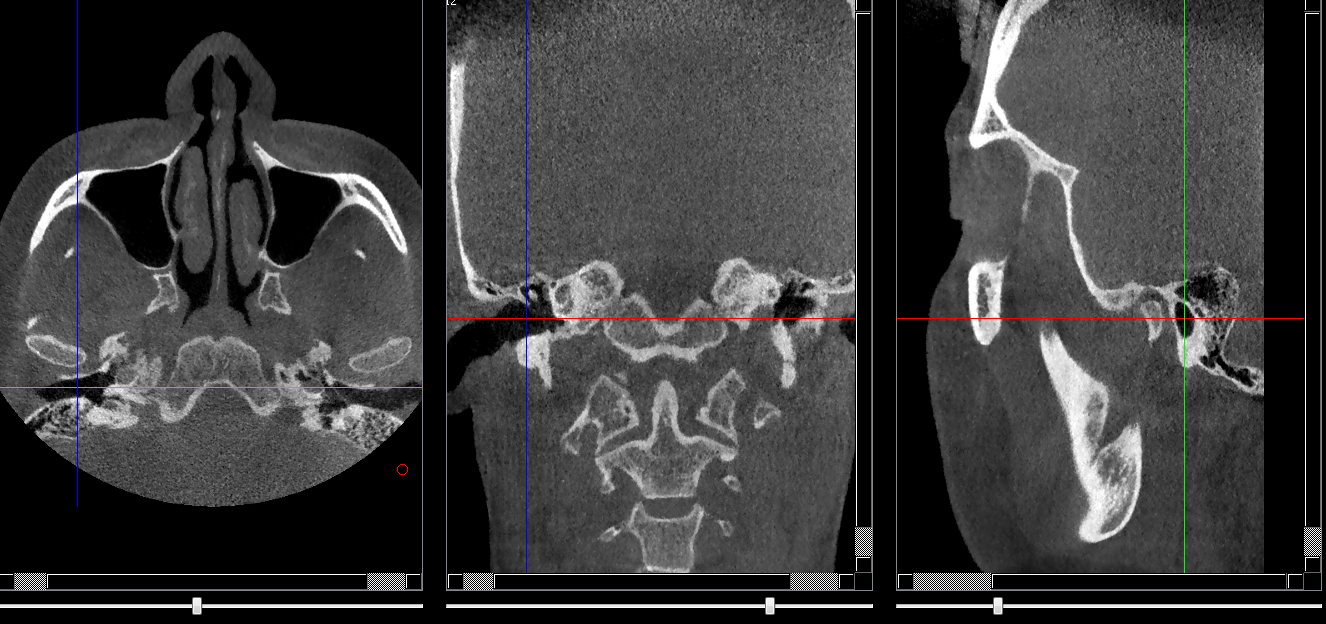

Structures osseuses

Méat acoustique externe

Repères anatomiques

- Coupe transversale

- Début : Conchlea

- Fin : Epine de l'os sphénoide

- Coupe frontale

- Début : Partie post du clivus

- Fin : Cellules mastoides

- Coupe saggitale

- Début : Cochlea

- Fin : Partie cutanée de l'oreille